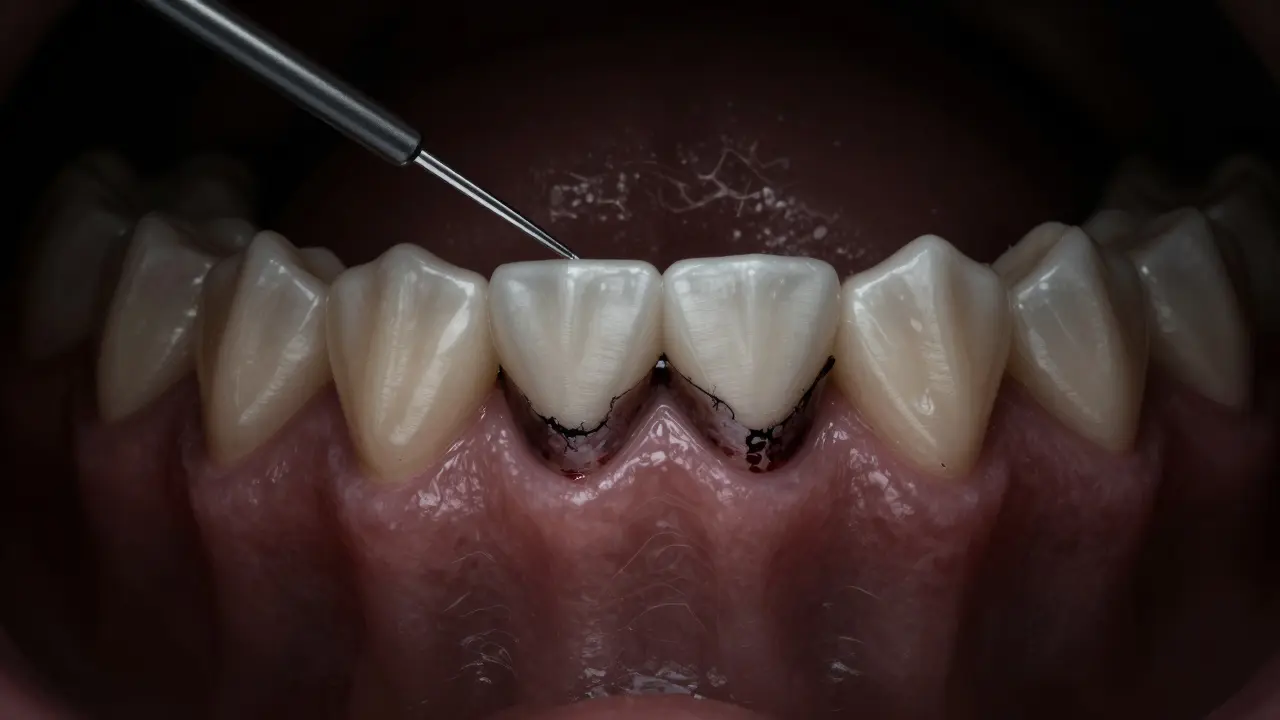

Druhý krok: Navštivte zubaře. Ne jako „když to už bolí“, ale jako preventivní návštěvu. Zubař použije speciální nástroj - sondu - kterou změří hloubku dásňového vaku. Pokud je hloubka větší než 3 mm, je to známka, že káž už začal poškozovat kost.

Třetí krok: Nechte provést skalpelování (tzv. „odstranění káže“). To není něco, co se dělá „jen tak“. Je to léčebný postup, který odstraňuje káž pod dásní. Někdy je potřeba i laserová léčba, ale to záleží na případu.